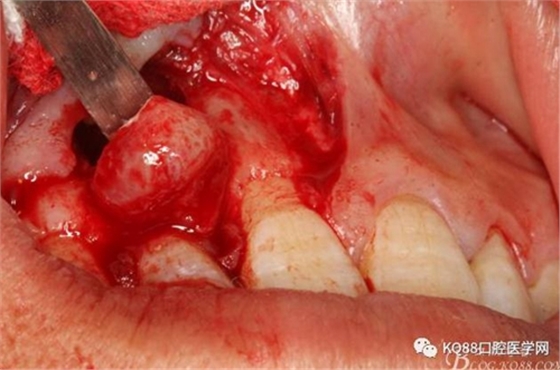

圖10。用骨膜剝離器沿著骨壁、緩慢逐漸剝離囊壁。

圖11。21囊壁被完整的剝離開(kāi)來(lái)。

圖12.摘除的12根尖區(qū)的囊壁組織。

圖13.囊壁摘除后形成的骨腔,12牙根完全裸露在骨腔內(nèi)。